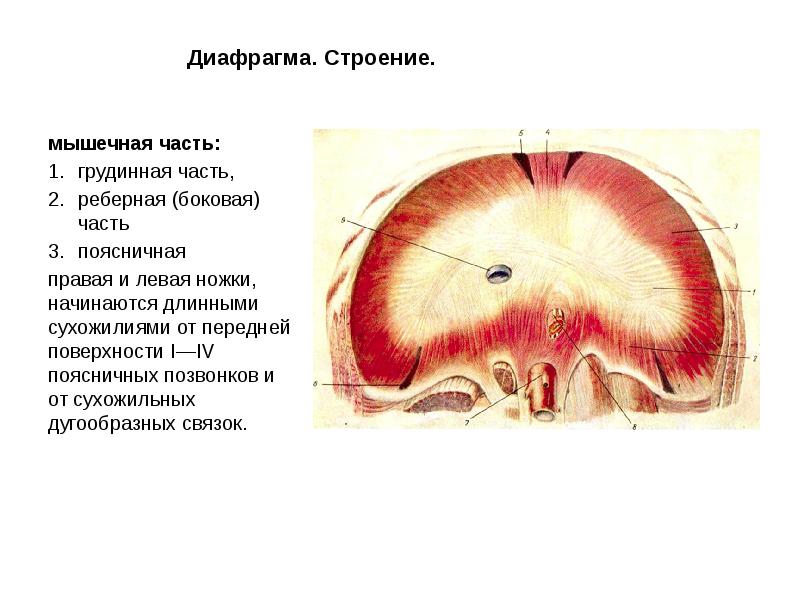

Анатомия диафрагмы и треугольника Бохдалека